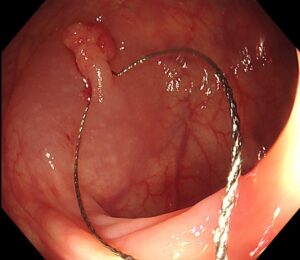

検査の結果、S状結腸に約12mmの有茎性ポリープ(Ip型) を発見しました🍄(写真1)

(写真1)

👉 スネア(リング状のワイヤー)をかけて(写真5)

(写真5)